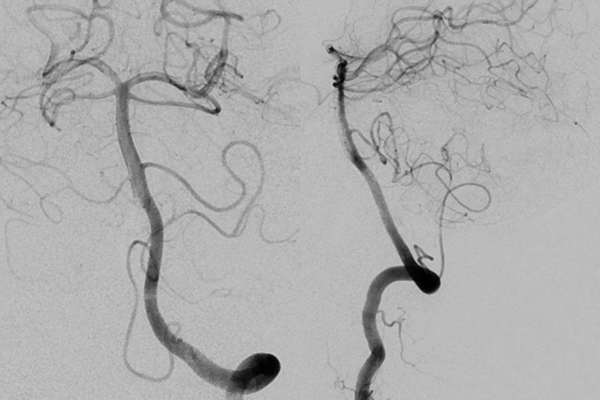

▲左侧椎动脉正侧位造影未见明显异常